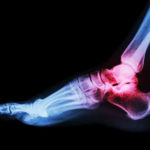

What Causes Ankle Arthritis?

When you hear the term arthritis, you probably think about it affecting your knee or the small joints in your hand, but arthritis is also pretty common in your ankles. Arthritis develops when the cartilage in your joints degenerates, making movements difficult and more painful. Since your ankle joints are used so frequently on a […]